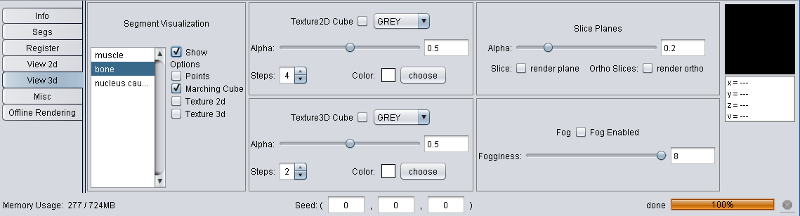

Since 3D segment rendering takes more time than 2d (strongly depending on your graphic card), the 3d visualization of a new segment is per default. Each segment can be shown or hidden using the "3d View" main menu or via the "View 3d" tool in the tool pane.

Currently four different segment visualization methods can be choosen.

The 3D segment visualization methods can be set for each individual segment. This can be done in the "view 3d" tool pane.

Experts Tip: The SegRenderer Settings allow to set much more options, e.g. the marching cube smoothing quality or the point distance.